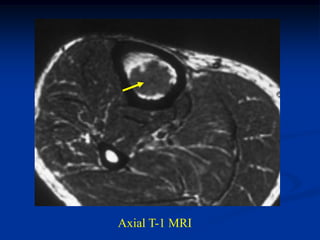

Case #608

17 year male with osteochondroma humerus

marrow

Axial T-1 MRI

cap

Sagittal T-1

MRI

Coronal T-2 MRI